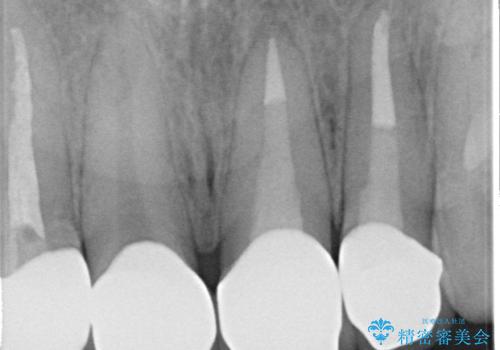

左上1、2の再根管治療終了後、オールセラミッククラウン(スペシャル)による補綴を行いました。

- オールセラミッククラウン(スペシャル)…¥130,000×4、仮歯…¥10,000×4、ファイバーコア…¥20,000×2費用は治療当時の料金となります